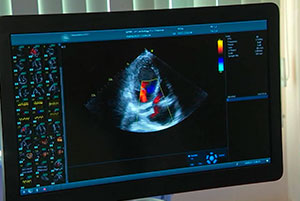

Национальный медицинский исследовательский центр кардиологии имени академика Чазова успешно лечит самые серьезные патологии, в том числе недостаточность клапанов — аортального и митрального, а с прошлого года еще и трикуспидального. Во многом благодаря нацпроекту «Новые технологии сбережения здоровья».

Комментируют руководитель отдела ультразвуковых методов исследования НМИЦ кардиологии им. ак. Е.И. Чазова Минздрава России Марина Саидова, руководитель лаборатории гибридных методов лечения ССЗ НМИЦ кардиологии им. ак. Е.И. Чазова Минздрава России Тимур Имаев, волонтер-медик по Калининградской области Карина Гзирян и координатор ВОД «Волонтеры-медики» по Республике Мордовия Варвара Терехина.